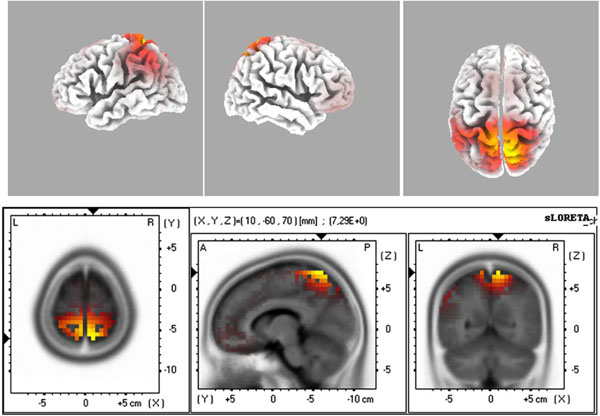

The source localization revealed BA6 as the major current density maxima in 6 out of 9 patients. The level of the propofol anesthesia is over the range of 1.2 µg/mL for these data sets (which coincided with the loss of consciousness). The spontaneous activity from every participant of the current study is included in the Appendix. The left column denotes the spectrograms. The sLORETA images and the maxima 3D coordinates as well as the Broadman areas are also provided. The locations from the maximal activity areas include, BA6 (5 subjects), BA9, BA10 (2 subjects), BA21 (2 subjects), BA24 (2 subjects), BA37. A sample is provided in Fig. (4), which presents activity at BA6 for the spindle oscillations during an unevoked condition.

The sLORETA image of maximal evoked activity at BA6. Upper panels indicate 3D representations and lower panel presents the sLORETA images with XYZ coordinates.

The evoked spindle oscillations displayed major activity localized at sources such as BA7 BA6, and BA10/11. These three locations (BA 6, 7, 11) and a location related to auditory cortex (BA42) were selected as regions of interest (ROI) in our study. The 3D representations were treated as set values and the GFP values were studied. Fig. (5) displays a sample source localization sLORETA image.

The sLORETA image of maximal evoked activity at BA7 (precuneus). Upper panels indicate 3D representations and lower panel presents the sLORETA images with XYZ coordinates.